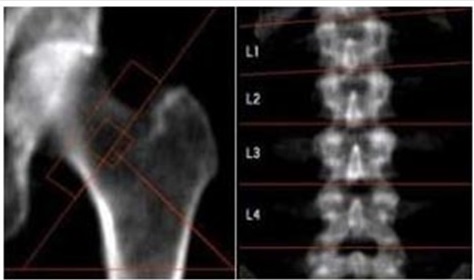

Osteoporosis, which means "porous bones", is a condition that causes bones to gradually thin and weaken, leaving them susceptible to fractures. Although all bones can be affected by the disease, those of the spine, hip and wrist are most likely to break. Spine and hip fractures are more dangerous as patients become bed ridden and develop lung infections and clots in their legs. Women are more susceptible because their bones tend to be lighter and less dense. Moreover, hormonal changes after menopause accelerate bone loss and make it weaker

Osteoporosis and Osteomalacia (which causes bones to soften) are common bone diseases that endocrinologists diagnose and treat. Osteoporosis is a disease that weakens your skeleton. Certain hormones like estrogen act to protect bone tissue. When hormone levels are abnormal or low, bones can lose calcium and gradually weaken. Menopause in women and loss of testicular function in men and aging may put you at risk for fractures. Endocrinologists treat other disorders that can affect bones such as metabolic bone disease, too much parathyroid hormone and bone issues secondary to long term use of steroids like prednisolone .